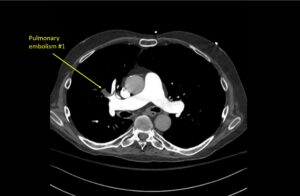

Wolff A, et al. Right atrial thrombosis. CT axial, 1

Wolff A et al. Right atrial thrombosis. CT axial 1